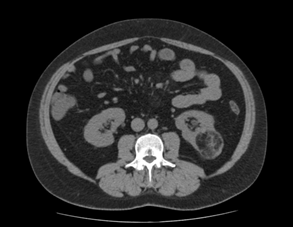

El paciente es derivado al Servicio de Urología para valoración y manejo. Se amplía el estudio con un TAC abdominal, que describe un angiomiolipoma en el polo inferior del riñón izquierdo, más precisamente en su aspecto posterior, con un tamaño aproximado de 6 cm en su eje mayor. El resto del estudio de imagen no presenta alteraciones significativas.

Tras discutir opciones terapéuticas y riesgos, se decide realizar embolización selectiva de la lesión, procedimiento que transcurre sin incidencias. En el control ecográfico realizado dos meses después, se objetiva una reducción del tamaño tumoral a 56 mm. Paralelamente, desde Urología se deriva a Nefrología para reevaluación de la HTA y ajuste terapéutico, ante la posibilidad de que el angiomiolipoma estuviera contribuyendo a la inestabilidad tensional.

Actualmente, el paciente permanece asintomático, en seguimiento por Urología, con un tamaño residual de la lesión de 37 mm. A nivel tensional, se observa una mejoría significativa tras la intervención, sin necesidad de modificar el tratamiento antihipertensivo previo.